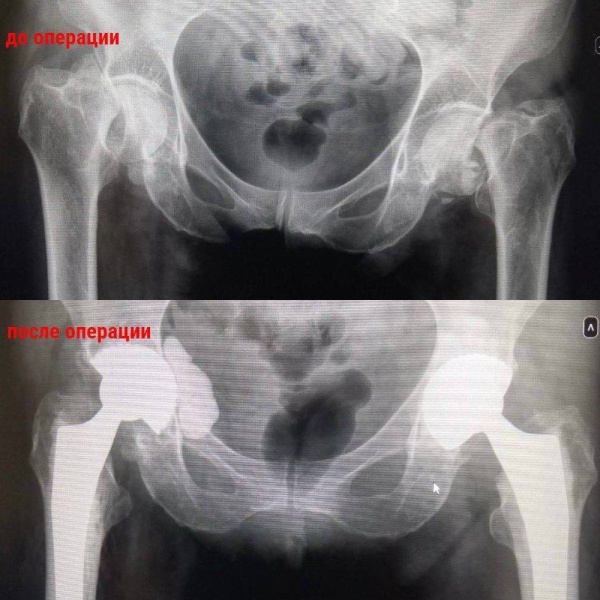

В Воскресенскую больницу поступила 61-летняя женщина с жалобами на боль в обоих тазобедренных суставах. Врачи обнаружили у пациентки перелом шейки бедра с двух сторон. Выяснилось, что у женщины  после неоднократной химиотерапии возник остеопороз – кальций стал вымываться из костей, случился перелом.

«Мы выполнили эндопротезирование тазобедренных суставов - заменили их протезными имплантами», - рассказал главный врач Воскресенской больницы Юрий Райхман.